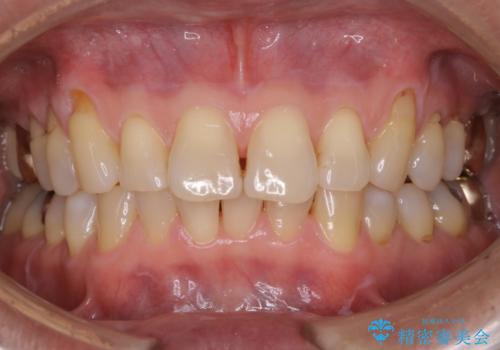

- 着色を落としてほしいとのことで1年ぶりに来院されました。

PMTC60分コースを行いました。

着色は、歯と歯の間と裏側に多く付いていました。

1年ぶりとなると、着色は層になり分厚く硬くなります。定期的にクリーニングをしてあげると良いかと思います。